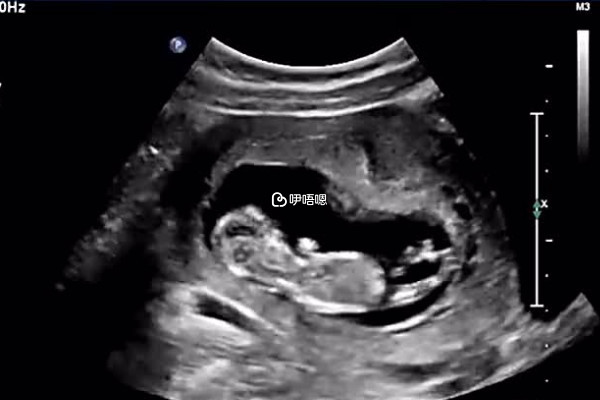

很多孕婦在懷孕之後都迫切的想要知道自己是懷的男孩還是女孩,所以就會想要通過一些方法來驗證胎兒的性別,在民間有很多方法都是可以用來判斷胎兒的性別是男是女的,下面就為大家詳細的講解一些49演算法閏月的具體計算方法,供大家參考: